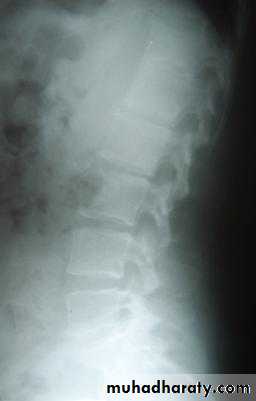

(3) Blood streams: it is by this route skeletal metastases occur. In order of the frequency the lumbar vertebrae, femur, thoracic vertebrae, rib and skull are affected and these deposits are generally osteolytic. Metastases may also commonly occur in the liver, lung, brain, and occasionally adrenal glands and ovaries.

This is described as cancer en-cuirasses when disease progress around chest wall. About 5% carcinoma in UK presented as locally advanced or symptoms of metastatic disease this figure is much higher in developing countries. These patients under goes staging evaluation so this will include a careful clinical examination, chest x-ray, CT scan chest and abdomen and isotope scan, bone scan.